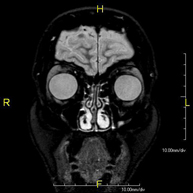

- RM Cerebral (craneal)

Prueba diagnóstica no invasiva que consiste en la obtención de imágenes de alta definición anatómica del cerebro mediante el empleo de un campo electromagnético y ondas de radio (con un emisor y un receptor). No utiliza radiación ionizante. Indicaciones: problemas vasculares, pérdida de memoria, epilepsia, cefalea, malformaciones, sospecha de tumor, meningitis. - RM Cais